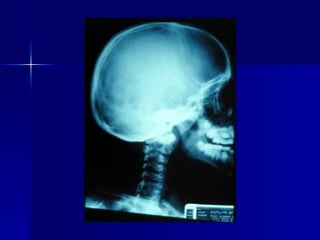

Cuadro clínico Hipertensión intracraneana Cefalea  Náuseas Vómito Hemianopsia bitemporal Rinorrea LCR Hipopituitarismo selectivo Panhipopituitarismo

Diagnóstico radiológico Resonancia magnética de cráneo Tomografía computarizada de cráneo Densitometría ósea de columna y cadera

Cuadro clínico de la acromegalia 19% Defectos en campos visuales 21% Bocio 28% Hipertensión  36% Impotencia 40% Parestesias/ S. túnel del carpo 55% Cefalea